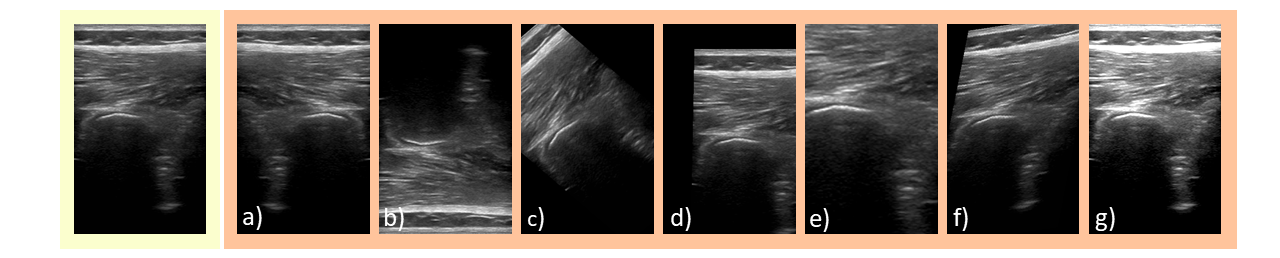

However, these classical augmentations are based on the mechanisms behind optical cameras which strongly differ from the principles of US. Applying these transformations to US scans could create unrealistic US images inconsistent with the real variability in US acquisitions. A horizontal flipping (Fig. 2 a)) of the US image is still consistent with a 180-degree rotation of the US transducer. A vertical flipping, however, would result in a shadowing region between a strong reflector and the transducer, as shown in Fig. 2 b) which does not reflect the physical model of attenuation. Rotations and translations of the image (shown in Fig. 2 c), d)) result in displacement between the location of the transducer at the top of the image and the image content, therefore creating a gap between the wave source and reflective tissue.

Refer to caption

Figure 2: Classical augmentations applied to an US image: a) horizontal flip, b) vertical flip, c) rotation, d) translation, e) scaling, f) shearing, g) brightness adaption.